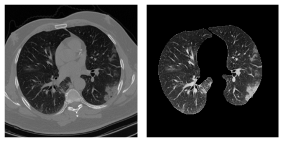

Refer to caption

Fig. 1: The segmented lung tissue using R231CovidWeb model.

3.2 Lung Segmentation

In order to remove the unimportant components and artifacts existing in a CT scan, we utilized a pre-trained U-Net-based lung region segmentation model [21] referred to as the “U-net (R231CovidWeb)”, which has been fine-tuned specifically on the COVID-19 images. A sample of lung region extracted by this model is illustrated in Fig. 1. It is worth mentioning that unlike segmenting infected regions, lung region segmentation is a well-studied topic and highly efficient models have been introduced so far. The input of the R231CovidWeb model is a CT scan with the original slice size of 512×512512512512\times 512. The model returns the extracted lung tissues, which will further go through some normalization and resizing steps. More specifically, the output images will be normalized between 00 and 111 to help the generalizability and effective convergence of the model. Following the literature [20, 25], we down-sampled the output images from the original 512×512512512512\times 512 size to 256×256256256256\times 256 to reduce the complexity and memory requirements with negligible loss of information. Finally, slices without visible lung tissues are excluded and the remaining ones are saved to be used in the CT-CAPS framework.